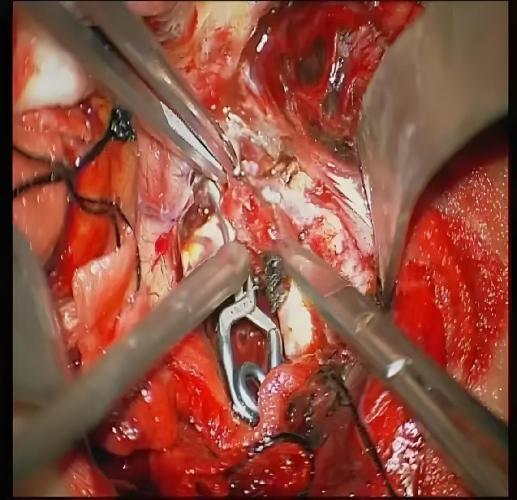

目的 探讨血清基质金属蛋白酶2(MMP-2)、髓过氧化物酶(MPO)、神经轴突导向因子3E(Sema3E)对全麻颅内动脉瘤夹闭术患者预后的预测价值。 方法 选取2023年5月至2025年5月张家口市第一医院收治125例全麻颅内动脉瘤夹闭术患者作为研究对象,根据术后1个月格拉斯哥预后评分(GOS),将1 ~ 3分的患者纳入预后不良组(29例),4 ~ 5分的患者纳入预后良好组(96例)。比较两组临床资料及血清MMP-2、MPO、Sema3E水平,并予以多因素logistic回归分析法分析全麻颅内动脉瘤夹闭术患者预后不良的危险因素,采用受试者工作特征(ROC)曲线分析血清MMP-2、MPO、Sema3E对全麻颅内动脉瘤夹闭术患者预后的预测价值,比较不同临床特征血清MMP-2、MPO、Sema3E水平,采用Spearman相关性分析血清MMP-2、MPO、Sema3E与临床特征的相关性。 结果 预后不良组Hunt-Hess分级Ⅲ级、术前GCS评分< 8分的患者占比为27.59%、51.72%,高于预后良好组的10.42%、5.21%(P < 0.05)。预后不良组血清MMP-2、MPO、Sema3E水平均高于预后良好组(P < 0.05)。血清MMP-2、MPO、Sema3E水平高是全麻颅内动脉瘤夹闭术患者预后不良的独立危险因素(OR = 1.087、2.807、2.079,P < 0.05)。血清MMP-2、MPO、Sema3E及联合检测预测全麻颅内动脉瘤夹闭术患者预后的曲线下面积(AUC)分别为0.747、0.690、0.656、0.809,诊断敏感度分别为72.41%、62.07%、68.97%、86.21%,特异度分别为72.92%、73.96%、66.67%、70.83%,其中联合检测的AUC最高(P < 0.05)。Hunt-Hess分级Ⅲ级患者血清MMP-2、MPO、Sema3E水平高于Ⅰ级、Ⅱ级患者,Ⅱ级患者高于Ⅰ级患者;术前GCS评分< 8分的患者血清MMP-2、MPO、Sema3E水平高于≥ 8分的患者(P < 0.05)。血清MMP-2、MPO、Sema3E与Hunt-Hess分级均呈正相关(r= 0.497、0.662、0.595,P < 0.05),与术前GCS评分均呈正相关(r = -0.547、-0.602、-0.697,P < 0.05)。 结论 全麻颅内动脉瘤夹闭术患者Hunt-Hess分级及术前GCS评分与预后具有一定联系,且血清MMP-2、MPO、Sema3E水平与Hunt-Hess分级、GCS评分密切相关,血清MMP-2、MPO、Sema3E水平高均为全麻颅内动脉瘤夹闭术患者预后不良的独立危险因素,且对患者预后具有较高预测价值,其中联合检测的预测价值最高。

Objective To explore the predictive value of serum matrix metalloproteinase-2 (MMP-2), myeloperoxidase (MPO), and axonal guidance factor 3E (Sema3E) in predicting the prognosis of patients undergoing intracranial aneurysm clipping surgery under general anesthesia. Methods A total of 125 patients who underwent general anesthesia for intracranial aneurysm clipping surgery at Zhangjiakou First Hospital from May 2023 to May 2025 were selected as the study subjects. Patients with Glasgow Outcome Scale (GOS) scores ranging from 1 to 3 one month after surgery were included in the poor prognosis group (29 cases), while those with scores from 4 to 5 were included in the good prognosis group (96 cases). The clinical data and the levels of serum MMP-2, MPO, and Sema3E were compared between the two groups. Multivariate logistic regression analysis was used to analyze the risk factors for poor prognosis in patients undergoing general anesthesia for intracranial aneurysm clipping surgery. Receiver Operating Characteristic (ROC) curves were employed to analyze the predictive value of serum MMP-2, MPO, and Sema3E for the prognosis of patients undergoing intracranial aneurysm clipping under general anesthesia. The levels of serum MMP-2, MPO, and Sema3E among patients with different clinical characteristics were compared. Spearman correlation analysis was conducted to investigate the correlation between serum MMP-2, MPO, and Sema3E and clinical features. Results The proportions of patients with Hunt-Hess grade Ⅲ and preoperative Glasgow Coma Scale (GCS) score < 8 in the poor prognosis group were 27.59% and 51.72%, respectively, which were higher than the 10.42% and 5.21% in the good prognosis group (P < 0.05). The levels of serum matrix metalloproteinase-2 (MMP-2), myeloperoxidase (MPO), and semaphorin 3E (Sema3E) in the poor prognosis group were higher than those in the good prognosis group (P < 0.05). High levels of serum MMP-2, MPO, and Sema3E were independent risk factors for poor prognosis in patients undergoing intracranial aneurysm clipping surgery under general anesthesia (OR = 1.087, 2.807, 2.079, P < 0.05). The areas under the curve (AUC) for predicting the prognosis of patients undergoing intracranial aneurysm clipping surgery under general anesthesia using serum MMP-2, MPO, Sema3E, and combined detection were 0.747, 0.690, 0.656, and 0.809, respectively. The diagnostic sensitivities were 72.41%, 62.07%, 68.97%, and 86.21%, and the specificities were 72.92%, 73.96%, 66.67%, and 70.83%, respectively. Among them, the AUC of combined detection was the highest (P < 0.05). The levels of serum MMP-2, MPO, and Sema3E in Hunt-Hess grade Ⅲ patients were higher than those in grade Ⅰ and Ⅱ patients, with grade Ⅱ patients having higher levels than grade Ⅰ patients. Patients with preoperative GCS scores < 8 had higher levels of serum MMP-2, MPO, and Sema3E than those with scores ≥ 8 (P < 0.05). Serum MMP-2, MPO, and Sema3E were positively correlated with Hunt-Hess grading (r = 0.497, 0.662, 0.595, 0.639, P < 0.05) and negatively correlated with scores of preoperative GCS (r = -0.547, -0.602, -0.697, -0.521, P < 0.05). Conclusions There was a certain correlation between Hunt-Hess grading, preoperative Glasgow Coma Scale (GCS) score, and the prognosis of patients undergoing intracranial aneurysm clipping surgery under general anesthesia. The levels of serum matrix metalloproteinase-2 (MMP-2), myeloperoxidase (MPO), and semaphorin 3E (Sema3E) were closely related to Hunt-Hess grading and GCS score. High levels of serum MMP-2, MPO, and Sema3E were independent risk factors for poor prognosis in patients undergoing intracranial aneurysm clipping surgery under general anesthesia and had high predictive value for patient prognosis. Among them, combined detection had the highest predictive value.